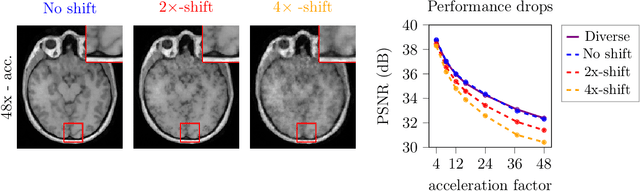

Abstract:Deep learning-based 3D imaging, in particular magnetic resonance imaging (MRI), is challenging because of limited availability of 3D training data. Therefore, 2D diffusion models trained on 2D slices are starting to be leveraged for 3D MRI reconstruction. However, as we show in this paper, existing methods pertain to a fixed voxel size, and performance degrades when the voxel size is varied, as it is often the case in clinical practice. In this paper, we propose and study several approaches for resolution-robust 3D MRI reconstruction with 2D diffusion priors. As a result of this investigation, we obtain a simple resolution-robust variational 3D reconstruction approach based on diffusion-guided regularization of randomly sampled 2D slices. This method provides competitive reconstruction quality compared to posterior sampling baselines. Towards resolving the sensitivity to resolution-shifts, we investigate state-of-the-art model-based approaches including Gaussian splatting, neural representations, and infinite-dimensional diffusion models, as well as a simple data-centric approach of training the diffusion model on several resolutions. Our experiments demonstrate that the model-based approaches fail to close the performance gap in 3D MRI. In contrast, the data-centric approach of training the diffusion model on various resolutions effectively provides a resolution-robust method without compromising accuracy.